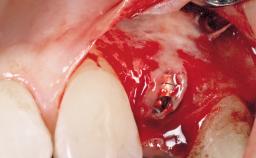

After flapless tooth removal and a healing period of 6 weeks a diameter-reduced two-piece implant is placed. The bone defect on the facial aspect is corrected with a contour augmentation using autologous bone chips covered with DBBM particles and a collagen membrane according to the Guided Bone Regeneration (GBR) approach.